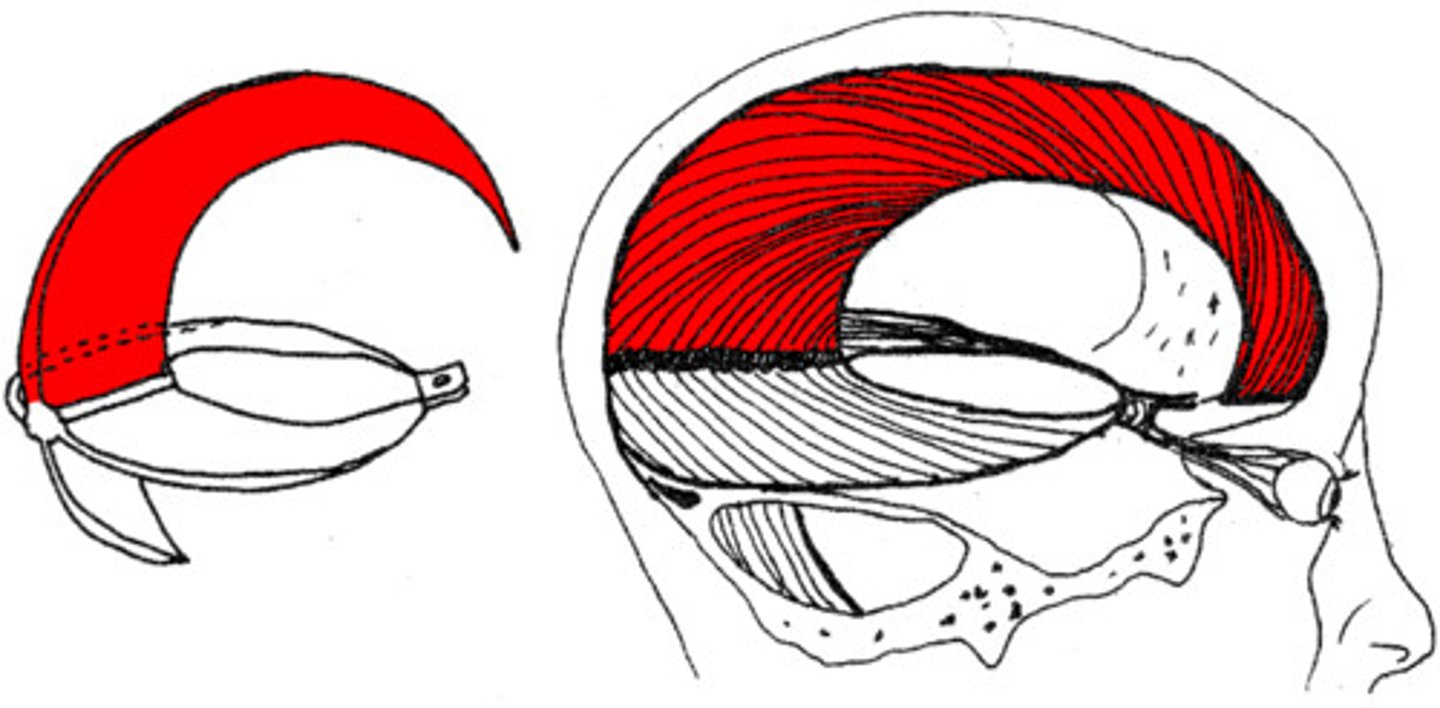

falx cerebri